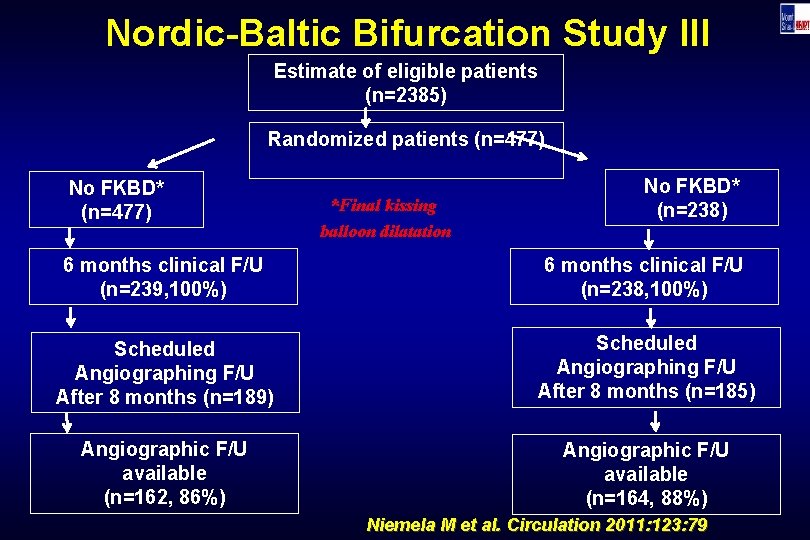

Nordic-Baltic Bifurcation Study III Estimate of eligible patients (n=2385) Randomized patients (n=477) No FKBD* (n=477) *Final kissing balloon dilatation No FKBD* (n=238) 6 months clinical F/U (n=239, 100%) 6 months clinical F/U (n=238, 100%) Scheduled Angiographing F/U After 8 months (n=189) Scheduled Angiographing F/U After 8 months (n=185) Angiographic F/U available (n=162, 86%) Angiographic F/U available (n=164, 88%) Niemela M et al. Circulation 2011: 123: 79